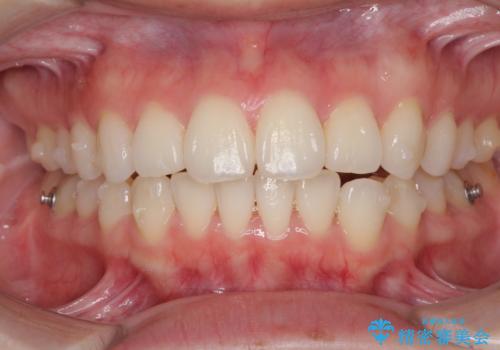

毎日しっかりと装着してくださったので、概ねシミュレーション通りに歯を移動させることができました。

治療前には接触することのなかった上下の前歯が接触するようになり、食事の際前歯でものをかみ切れるようになりました。

気にしていた口元の印象が改善され、患者様には大変満足していただきました。